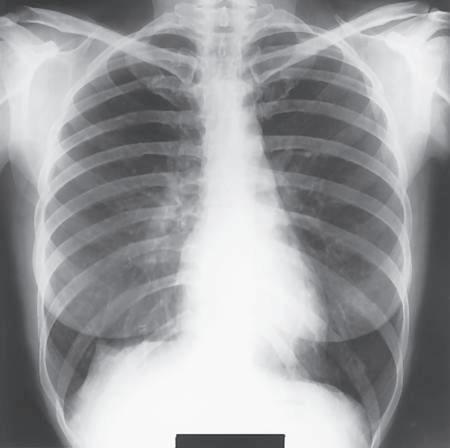

General Terms Radiograph (ra′-de-o-graf ): An image of a patient’s anatomic part(s), as produced by the action of x-rays on an image receptor (Fig. 1-33). If the radiograph is produced with the use of traditional film-screen technology, the image is stored and displayed on film; if the radiograph is produced via digital technology, the image is viewed and stored with the use of computers. Radiography (ra˝-de-og′-rah-fe): The process and procedures of producing a radiograph. Radiograph versus x-ray film: In practice, the terms radiograph and x-ray film (or just film) are often used interchangeably. However, x-ray film specifically refers to the physical piece of material on which a latent (nonprocessed) radiographic image is stored. The term radiograph includes the recording medium and the image. Image receptor (IR): The device that captures the radiographic image that exits the patient; refers to both film-screen cassettes and digital acquisition devices. Central ray (CR): Refers to the center-most portion of the x-ray beam emitted from the x-ray tube; the portion of the x-ray beam that has the least divergence. Radiographic examination or procedure

A radiologic technologist is shown positioning the patient for a routine chest examination or procedure (Fig. 1-34). A radiographic examination involves five general functions: 1. Positioning of body part and alignment with the IR and CR 2. Application of radiation protection measures and devices 3. Selection of exposure factors (radiographic technique) on the control panel 4. Instructions to the patient related to respiration (breathing) and initiation of the x-ray exposure 5. Processing of the IR (film-based [analog] and cassette-based [PSP] system)

Fig. 1-33 Chest radiograph.